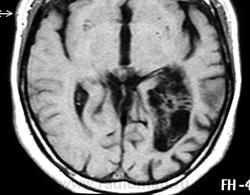

ГМ. Субэпендимома 2. +

Субэпендимома